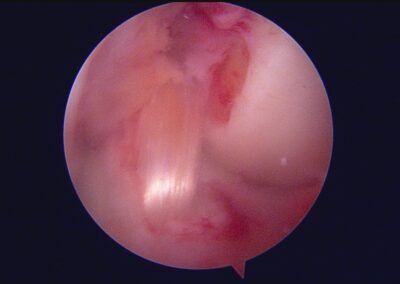

GalleryShoulder rotator cuff repair Meniscus root repair Meniscus repair Bankart repair for recurrent shoulder dislocation ACL reconstruction Machines Instruments